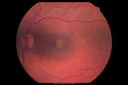

Best Disease - Color Fundus Photo814 views00000

best_maga_02.png

Best Disease - Color Fundus Photo710 views00000